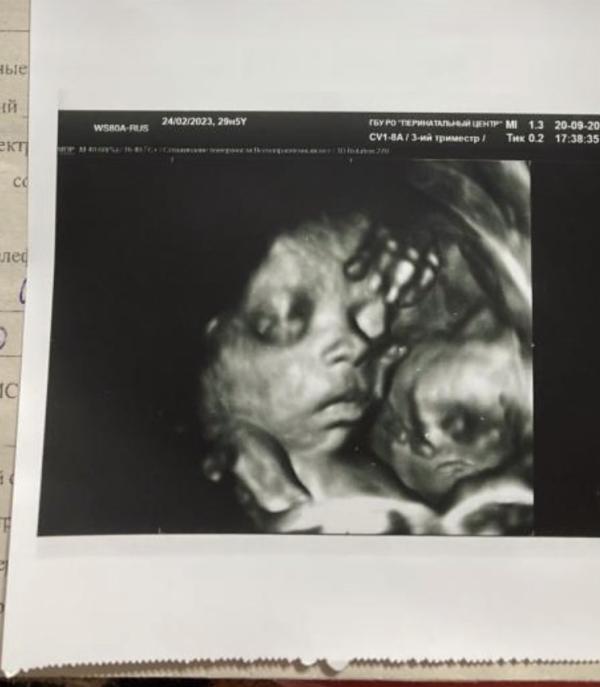

(на втором фото

-вес 1270

-29,5 недель)

Интересная фотка, на второй картинке кажется еще что то типа куклы 🙂